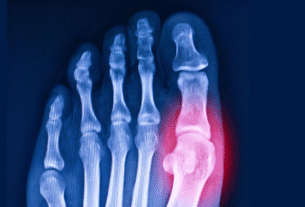

Al igual que en los humanos, este tejido adiposo es biológicamente activo. Produce hormonas inflamatorias que degradan el cuerpo desde adentro hacia afuera, provocando osteoartritis, hipertensión arterial y, quizás la más crítica, diabetes tipo 2. Y al igual que los humanos, estos gatos se beneficiarían enormemente de una dieta más baja en calorías.